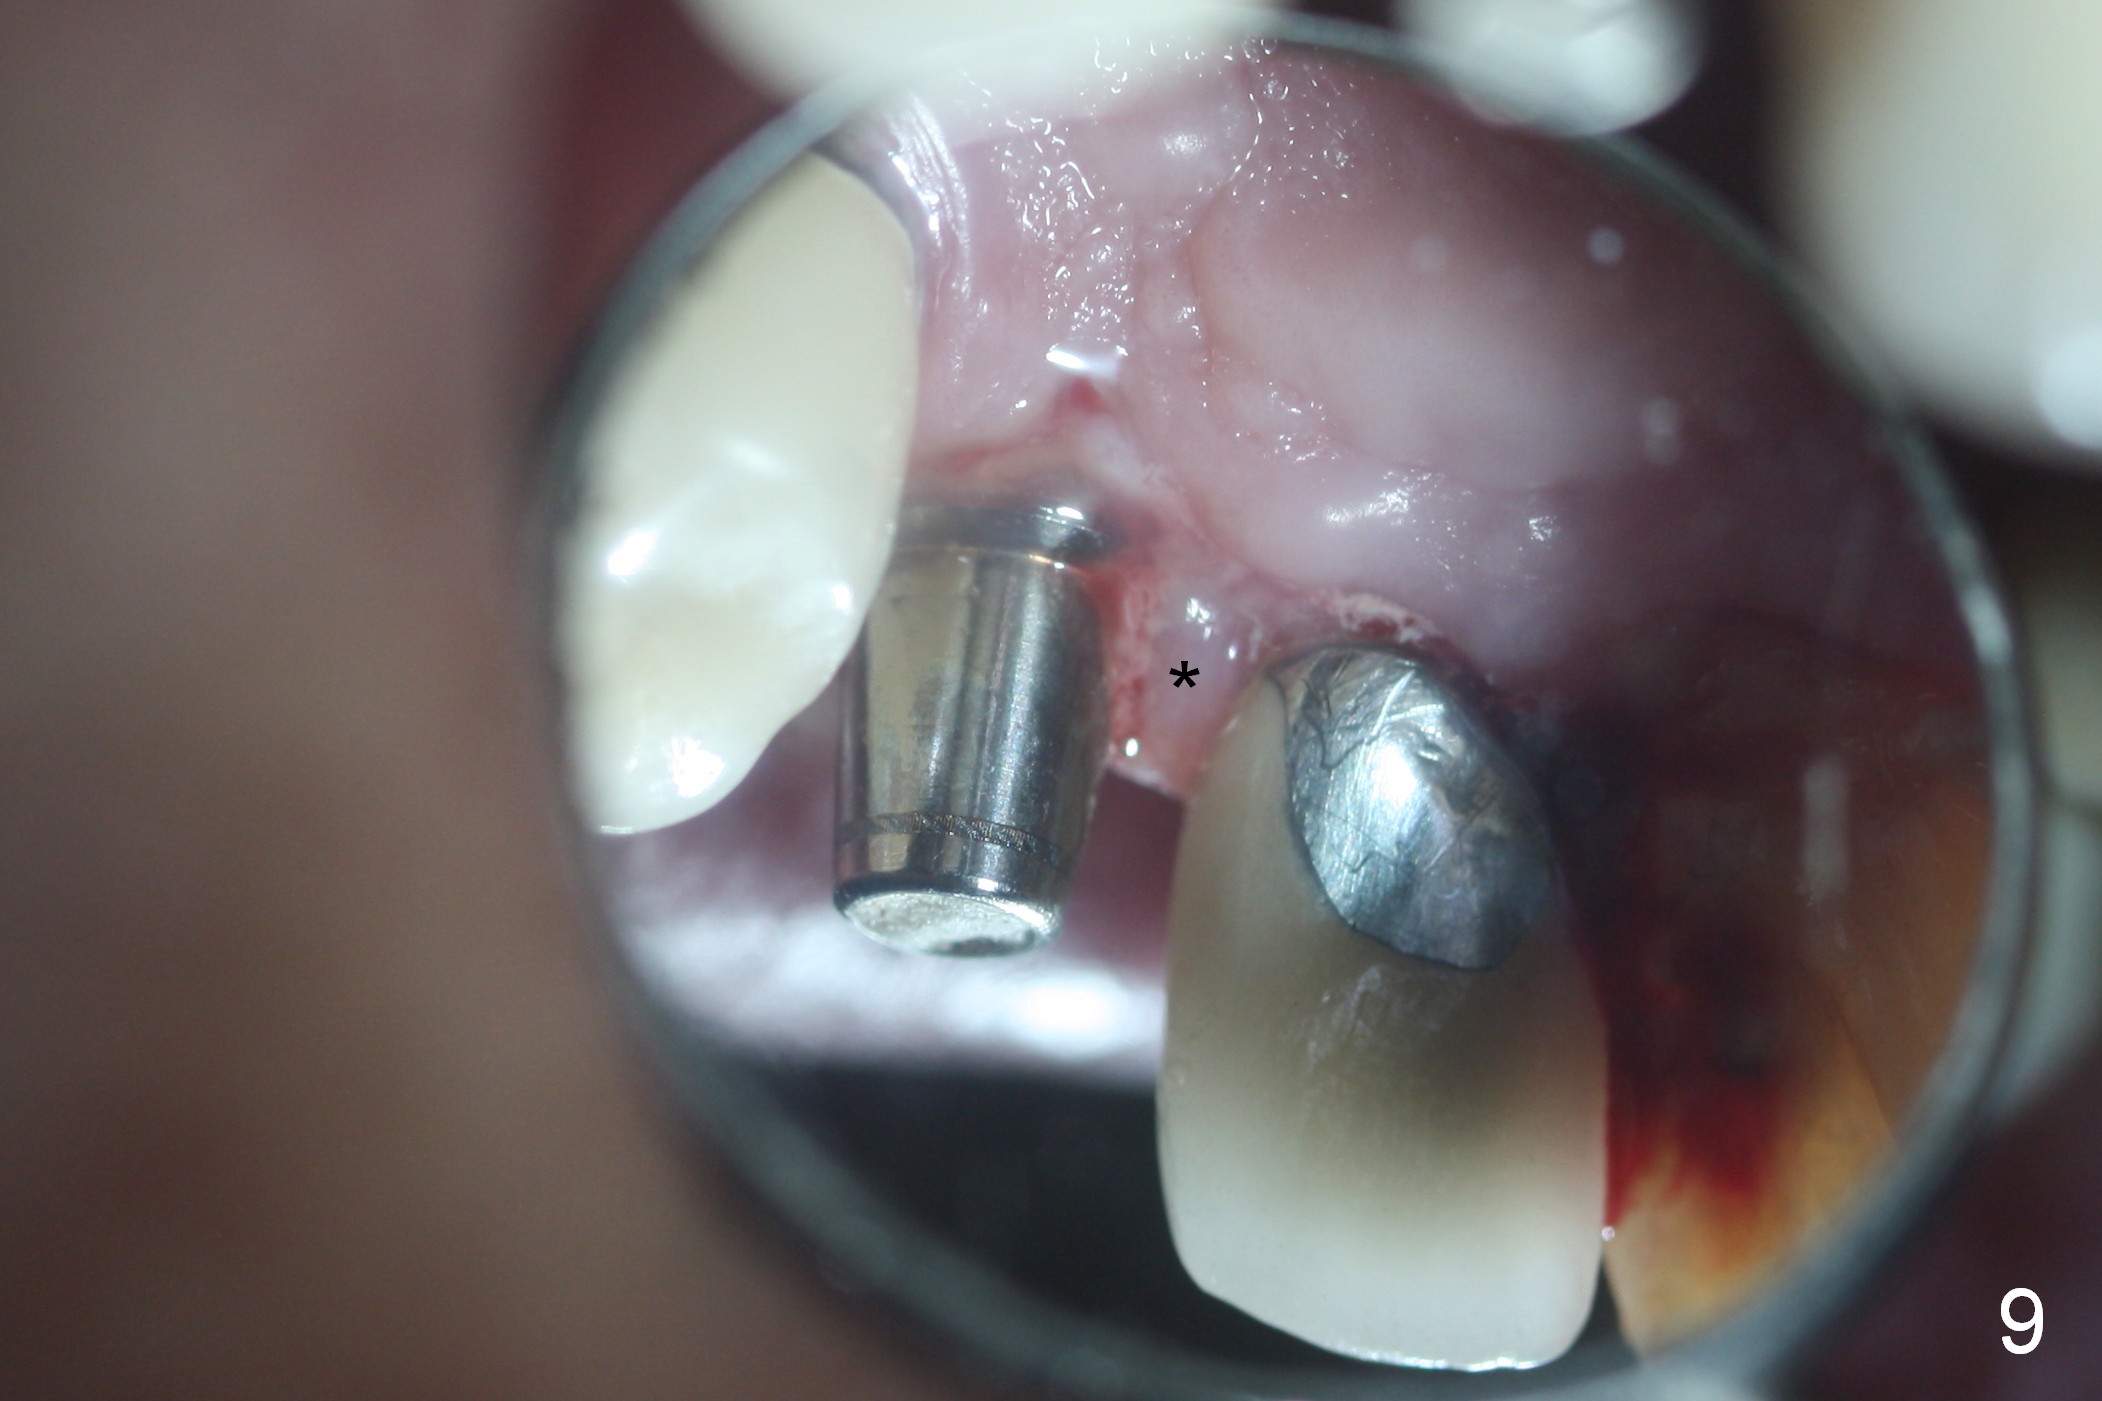

After extraction of the subgingival fractured upper right canine (Fig.1), the buccal plate is found to have been perforated at the apex. the root is measured 5x12 mm. Initial osteotomy with a 2 mm pilot drill shows that the bone is soft (Fig.2). After use of a 3.2 mm drill (underprep, normal drill size (3.7 mm)), a 4.5x15 mm implant is placed with insertion torque > 50 Ncm (Fig.3). The implant is further torqued until the implant plateau is 3 mm apical to the buccal gingival margin; a 5.5x5(3) mm abutment is placed (Fig.4,5 A). Osteogen plug is inserted into the apex of the socket, while the rest of gap is filled with mineralized cortical allograft and Osteogen. An immediate provisional (Fig.5,6 P) is fabricated to keep the graft in place, followed by periodontal dressing (Fig.6).